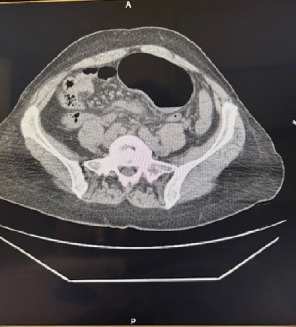

Introduction: Volvulus of the caecum, ascending colon and first third of the transverse colon is a very rare surgical emergency. Timely diagnosis and intervention can avert serious complications. Case Report: A 54-year-old woman presented to the emergency department with colicky epigastric pain radiating to the left iliac fossa that lasted for 12 h. Vital signs were stable upon arrival at the hospital. Physical examination revealed that left abdomen and suprapubic fullness and bowel sounds were recorded, and rebound tests were negative. Laboratory results were neutrophils: 78% (35%-72%), lymphocytes: 16% (20%-45%), HB: 11 g/dL (12-16), HCT: 33% (36%-48%); all the rest were normal. Furthermore, computed tomography revealed a distended close of the large bowel extending from the left hypochondrium to the left iliac fossa. During explorative laparotomy, volvulus of the first third of the transverse, ascending colon and caecum was detected. Because the viability of the bowel wall was compromised, right extended hemicolectomy was performed with consequent ileotransverse anastomosis. The postoperative period was uneventful, and the patient was discharged on the fourth postoperative day. Conclusions: Expeditious diagnosis and early intervention of very rare surgical emergencies such as ascending colon volvulus may avert disastrous complications.

Abstract Image